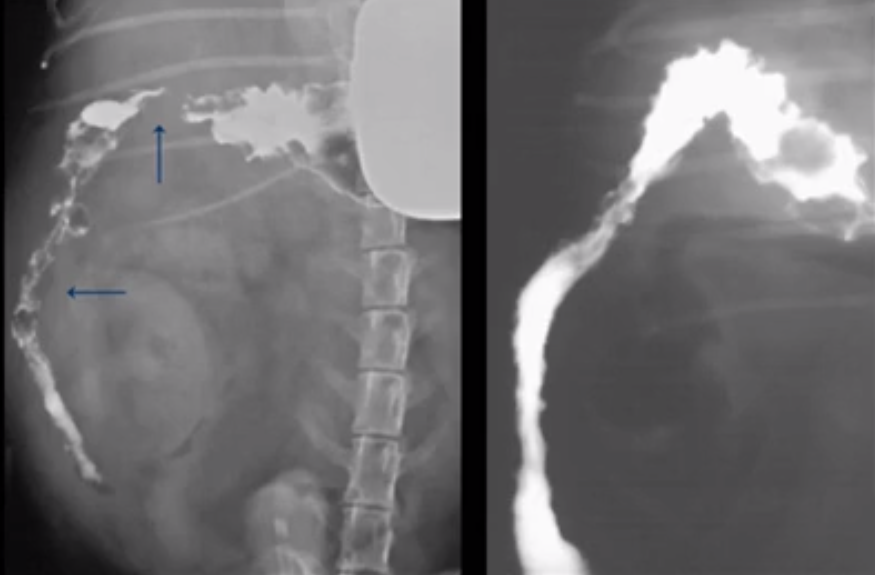

What does this image show?

Gravel sign of partial obstruction

Linear FB - plicated SI moved to one side of the body

FB consistently seen between views